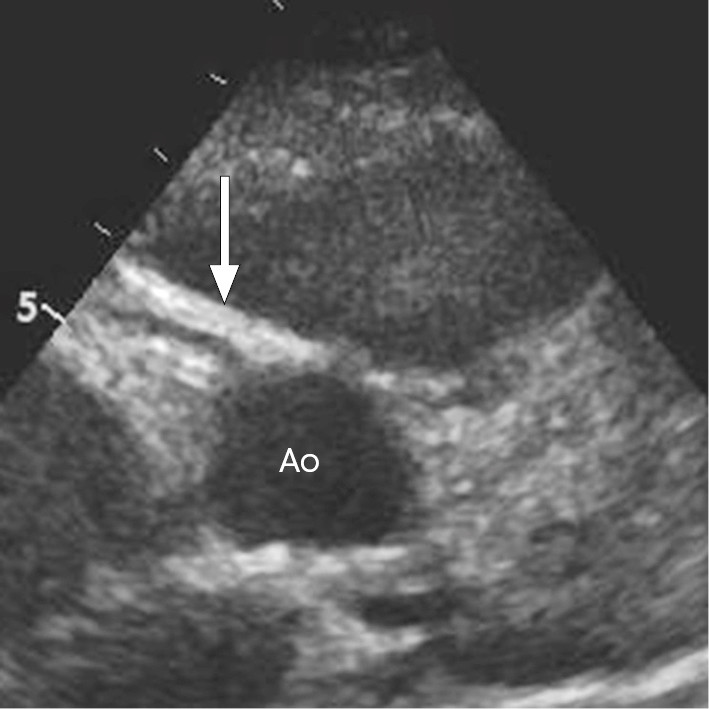

On day 4, echocardiography showed increased echo in the coronary artery wall, which may be an early sign of cardiac involvement (Figure 1). Inflammatory markers had fallen nicely after the first dose of immunoglobulins, but the fever persisted. The patient was therefore started on oral acetylsalicylic acid 500 mg × 4 daily. On day 5, a second equivalent dose of immunoglobulins was administered and the patient became afebrile.

Figure 1 Echocardiogram of the aorta in cross-section (Ao) showing the exit point of the right coronary artery (arrow). The right coronary artery has increased echo in the vessel wall, which can be seen in the acute stage of Kawasaki syndrome.